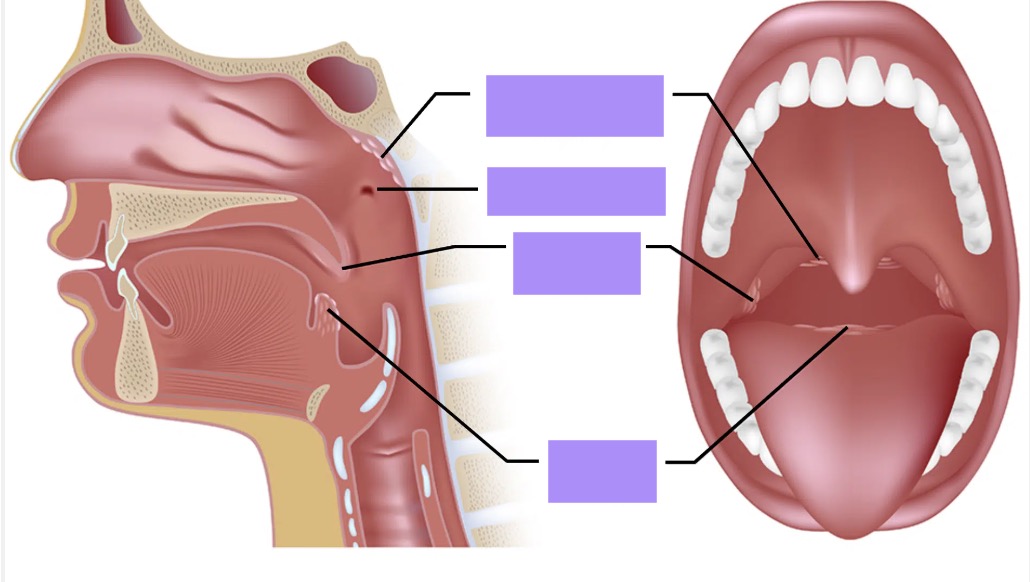

tonsils: state the groups of tonsillar tissue

4 groups of tonsillar tissue

palatine tonsils - paired

pharyngeal tonsils/ adenoids - unpaired

lingual tonsils - paired

tubal tonsils - paired

tonsils: palatine tonsils location

palatine tonsils location

between the palatoglossal (anterior) and palatopharyngeal (posterior) arches

oropharynx

tonsils: pharyngeal tonsils/ adenoids location

pharyngeal tonsils/ adenoids location

the posterior wall of the nasopharynx

tonsils: lingual tonsils location

lingual tonsils location

underneath the mucosa of the posterior 1/3 of tongue

tonsils: tubal tonsils location

tubal tonsils location

around the entrance to the auditory/ Eustachian tube

MAY OR MAY NOT BE PRESENT